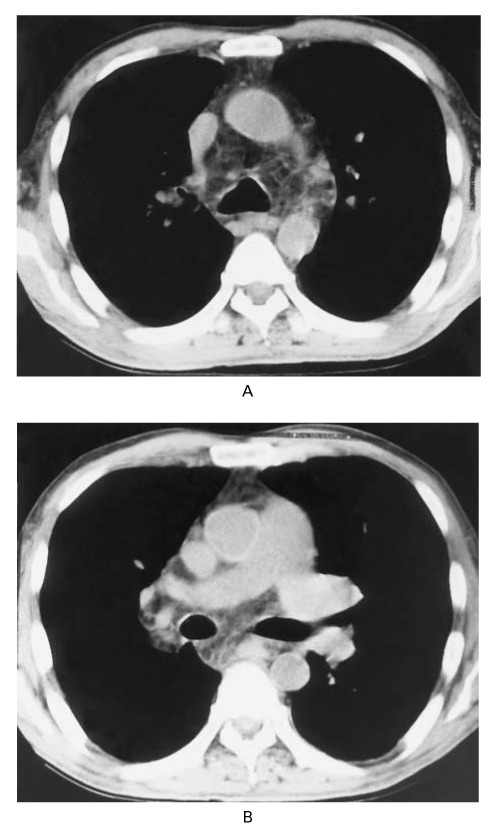

A chest x-ray (Panel A), CT scan of the chest (Panel B) and abdomen (Panel C),

and the results of a barium-enema examination of the small bowel (Panel D) are shown

below.

Panel A.

Panel B